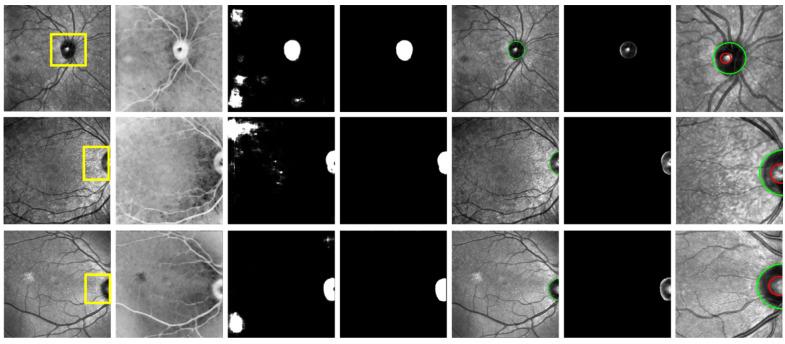

Multiple sclerosis (MS), a chronic disease of the central nervous system, is known to cause structural and vascular changes in the retina. Although optical coherence tomography (OCT) and fundus photography can detect retinal thinning and circulatory abnormalities, these findings are not specific to MS. This study explores the potential of Infrared Scanning-Laser-Ophthalmoscopy (IR-SLO) imaging to uncover vascular morphological features that may serve as MS-specific biomarkers. Using an age-matched, subject-wise stratified k-fold cross-validation approach, a deep learning model originally designed for color fundus images was adapted to segment optic disc, optic cup, and retinal vessels in IR-SLO images, achieving Dice coefficients of 91%, 94.5%, and 97%, respectively. This process included tailored pre- and post-processing steps to optimize segmentation accuracy. Subsequently, clinically relevant features were extracted. Statistical analyses followed by SHapley Additive exPlanations (SHAP) identified vessel fractal dimension, vessel density in zones B and C (circular regions extending 0.5-1 and 0.5-2 optic disc diameters from the optic disc margin, respectively), along with vessel intensity and width, as key differentiators between MS patients and healthy controls. These findings suggest that IR-SLO can non-invasively detect retinal vascular biomarkers that may serve as additional or alternative diagnostic markers for MS diagnosis, complementing current invasive procedures.

多发性硬化症(MS)是一种中枢神经系统的慢性疾病,已知会导致视网膜的结构和血管变化。尽管光学相干断层扫描(OCT)和眼底摄影可以检测到视网膜变薄和循环异常,但这些发现并非MS所特有。本研究探讨了红外扫描激光检眼镜(IR-SLO)成像揭示可能作为MS特异性生物标志物的血管形态特征的潜力。使用年龄匹配、按受试者分层的k折交叉验证方法,将最初为彩色眼底图像设计的深度学习模型进行调整,以分割IR-SLO图像中的视盘、视杯和视网膜血管,Dice系数分别达到91%、94.5%和97%。这一过程包括定制的预处理和后处理步骤,以优化分割精度。随后,提取临床相关特征。通过统计分析和SHapley加性解释(SHAP),确定血管分形维数、B区和C区(分别从视盘边缘延伸0.5-1和0.5-2个视盘直径的圆形区域)的血管密度,以及血管强度和宽度,是MS患者与健康对照之间的关键区分因素。这些发现表明,IR-SLO可以无创检测视网膜血管生物标志物,这些标志物可作为MS诊断的额外或替代诊断标志物,补充当前的侵入性检查方法。